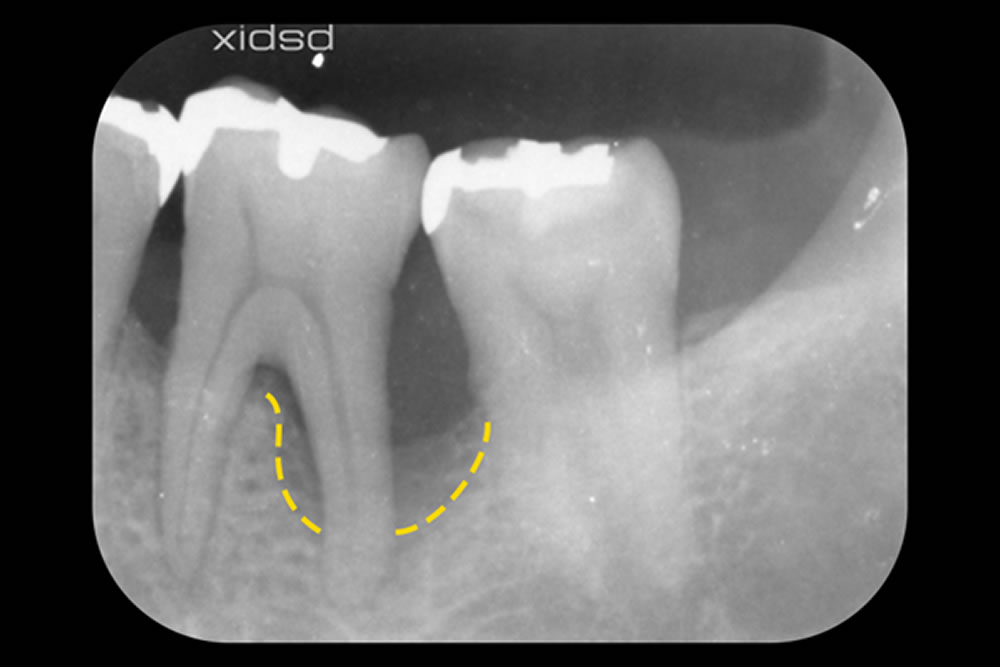

こちらの患者さまは、左下の奥歯の歯の根の分かれ目(分岐部)と、その外側(頬側)に、骨が深く失われた「垂直性骨欠損」が確認されました。